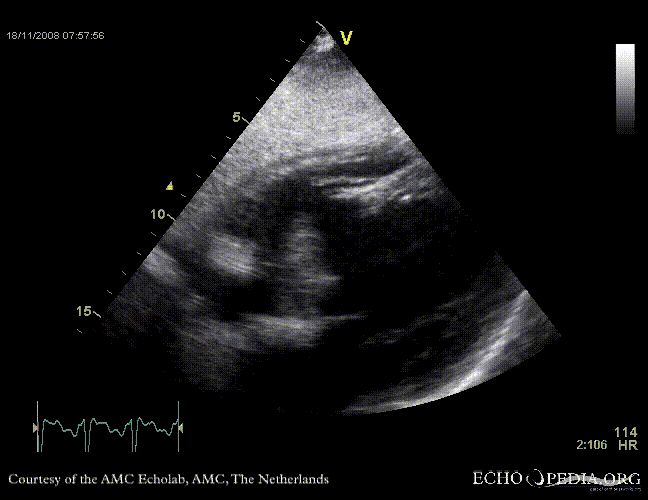

Rupture of the ventricular septum

VSR 3